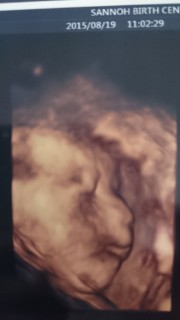

2人目で念願の女の子。 横顔美人さん(*^^*)笑 体重は1208グラムで順調でした。